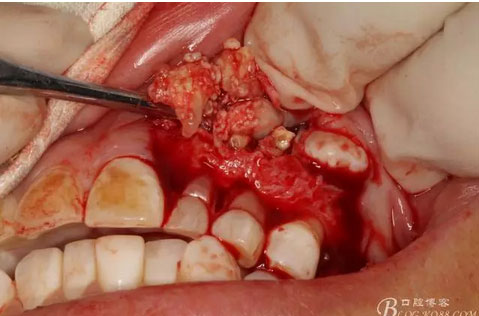

圖13.暴露出部分牙瘤

圖15.剝離出來的多個(gè)成型小牙齒及致密鈣化物。

圖17.呼之欲出的巨大牙瘤組織。